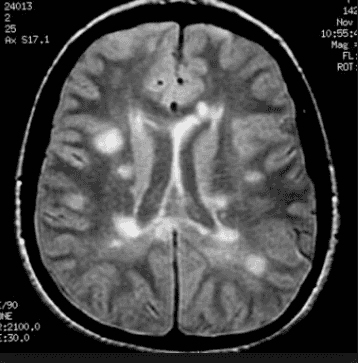

Given below is the X-ray image of the brain. Which of the following transformations you will use to remove just the outer skull keeping the dimension of the brain same.

- Here, Opening will be used.

- First, erosion will be used to remove the white skull portion.

- But this will also shrink the size of the brain.

- To make the dimension of the brain same, dilation will be used.

- Non-natural images are usually specific to the range of the values that they lie between - dividing by 255 distorts the data of this image (e.g. some MRI regions have pixels that never reach 255, and hence 255 is an arbitrary value.)